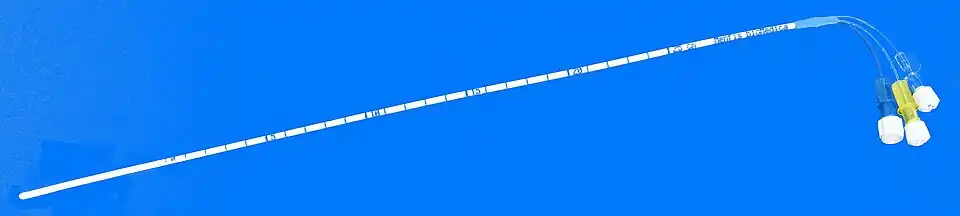

Для непосредственной регистрации моторной активности органов желудочно-кишечного тракта наибольшее распространение получила манометрия, выполняемая с помощью многоканального водно-перфузионного катетера. Выделяют следующие виды манометрии: манометрию пищевода, антродуоденальную манометрию, манометрию сфинктера Одди, толстокишечную и аноректальную манометрию. Манометрия пищевода показана перед операционными вмешательствами в области гастроэзофагеального перехода, при аномалиях верхнего пищеводного сфинктера (ВПС) и глотки, исследовании давления нижнего пищеводного сфинктера (НПС), первичных расстройствах моторики пищевода (кардиоспазм, ахалазия кардии, дискинезия пищевода, диффузный спазм пищевода, гипертонус НПС), оценке дефектов перистальтики[15]. Показаниям к проведению манометрии сфинктера Одди: постхолецистэктомический синдром, холангит, спазм сфинктера Одди, закупорка жёлчного протока и др. Аноректальная и/или толстокишечная манометрия проводится по следующим показаниям: запоры, резистентные к проводимой терапии, дифференциальная диагностика хронической кишечной псевдообструкции, необъяснимые причины нарушения моторики толстой кишки, отсутствие расслабления внутреннего сфинктера заднего прохода, перед и после оперативного вмешательства, в процессе биофидбэк-терапии по поводу недержания кала и функциональных запорах[21][27].

- Гастроинтестинальная манометрия

Гастроманограф для перфузионной гастроинтестинальной манометрии

Гастроманограф для перфузионной гастроинтестинальной манометрии Балонный катетер для аноректальной манометрии

Балонный катетер для аноректальной манометрии Манометрия пищевода. Показано прохождение глотка воды

Манометрия пищевода. Показано прохождение глотка воды- Условный график давления при манометрии сфинктера Одди

См. также